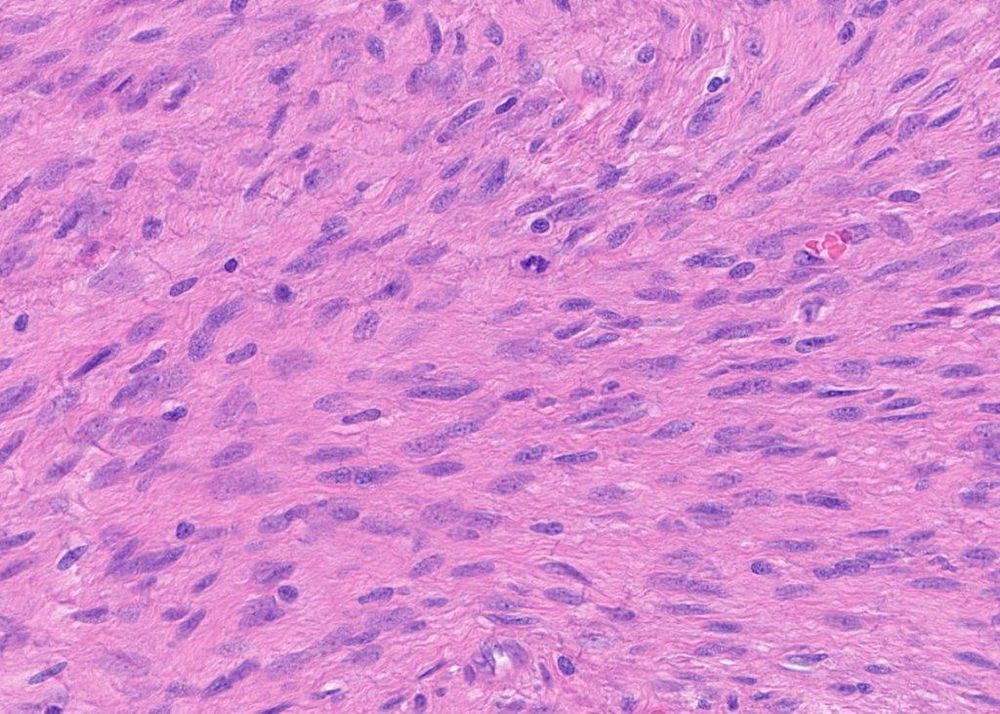

This is classic morphology for a GLI1 coamplified differentiated liposarcoma with perineurial-like whorls. So now the MDM2 amplification makes sense. The current tumor is showing essentially classical features of a GLI1 amplified soft tissue sarcoma. So the morphology/molecular explain each other.

12.06.2025 21:10 β€” πŸ‘ 5    πŸ” 1    πŸ’¬ 1    πŸ“Œ 0